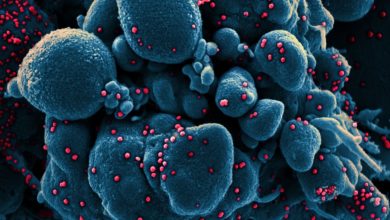

Coronavírus pode infectar intestino, além de pulmões, diz pesquisa

Pesquisadores holandeses publicaram um estudo, no dia 1º de maio, na revista Sciece, confirmando que o intestino também é atingido…

Especialistas tentam traçar a ‘árvore genealógica’ genética do novo coronavírus para datar seu surgimento

Para a China e para cada país afetado pela Covid-19, a data dos primeiros casos está clara. Mas o vírus…

Pandemia da covid-19 deve durar dois anos, dizem especialistas

A pandemia provocada pelo coronavírus deve durar dois anos e não deve ser controlada até que dois terços da população…

Os fumantes parecem estar mais protegidos contra o coronavírus. Por quê?

Dentre os inúmeros estudos em curso tentando mapear a penetração do coronavírus em diferentes estratos da população, um em específico…